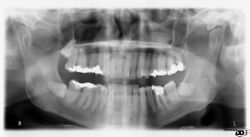

A dental panoramic radiograph, showing the maxilla and mandible, all the teeth including the "wisdom teeth," the frontal and maxillary sinuses, the nasal cavity and the temporomandibular joint and other near by head and neck anatomy.